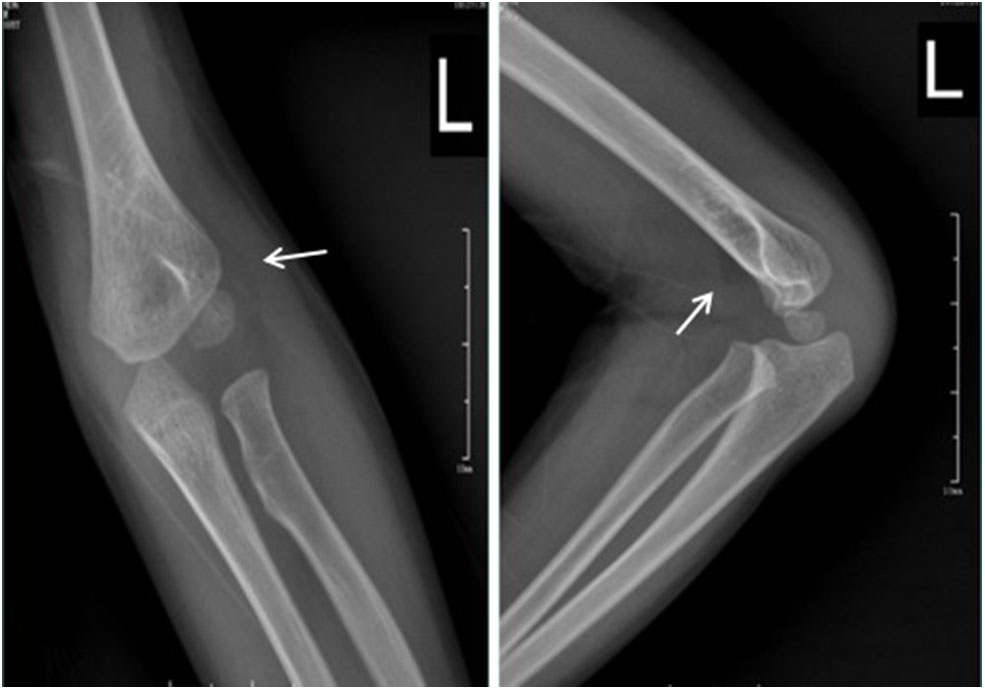

A total of 43,560 pediatric patients with AEI were enrolled, of whom 5,466 patients were diagnosed with fracture, 4,916 of which were confirmed by initial plain radiographs, and 550 were occult fractures confirmed by immediate MRI, immediate CT, or late radiographs 2 weeks post-injury. The mean age of the occult fracture patients was 7.9 years (range 1.6–14 years). The distribution of fractures diagnosed by initial plain radiographs and the distribution and rate of occult fractures in the extremities is summarized in Table 1. The prevalence of occult fractures of the extremities was 10.1% (550/5,466). The history and physical examination findings of all 550 patients led the orthopedic surgeons to suspect a possible fracture although there were no visible signs of fracture on the initial anteroposterior and lateral radiographs. Immediate MRI (n = 193) (Figure 1), immediate CT (n = 199) (Figure 2), or late radiographs (n = 158) (Figure 3) finally confirmed these occult fractures. The physical examination of the 550 patients revealed abnormal soft tissue swelling, persistent pressure pain at the trauma site, and limited active and passive motion because of pain. For patients with distal humerus injury, their anteroposterior and lateral radiographic views showed displacement of the fat pads (fat pad sign) due to joint effusion, which is an indirect sign of fracture (Figure 4).

FIGURE 2

www.frontiersin.org

Figure 2. Standard radiographs of the ankle in AP and LL projections did not reveal a fracture. CT showed a small fracture in the distal fibula (arrow).